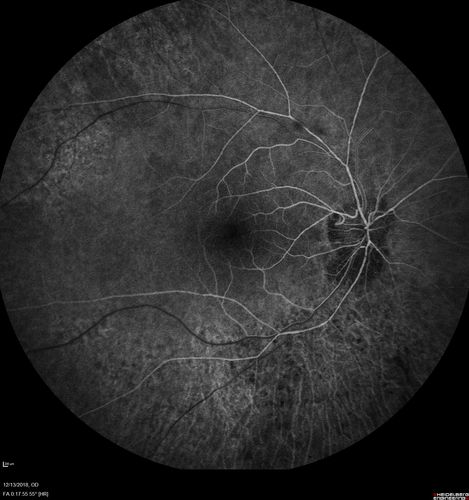

Retinitis Pigmentosa with Cystoid Macular Edema responsive to topical carbonic anhydrase inhibitors

67 year old female  She thought it was time to have her glasses changed.She has no family history of reitnal disease and has never been diagnosed with a problem.   She started having night vision trouble the last year.  Two sisters and a brother with normal vision.

VA OD: Dcc20/40-2 NccJ3

VA OS: Dcc20/20 NccJ1

IOP: TP: OD:9